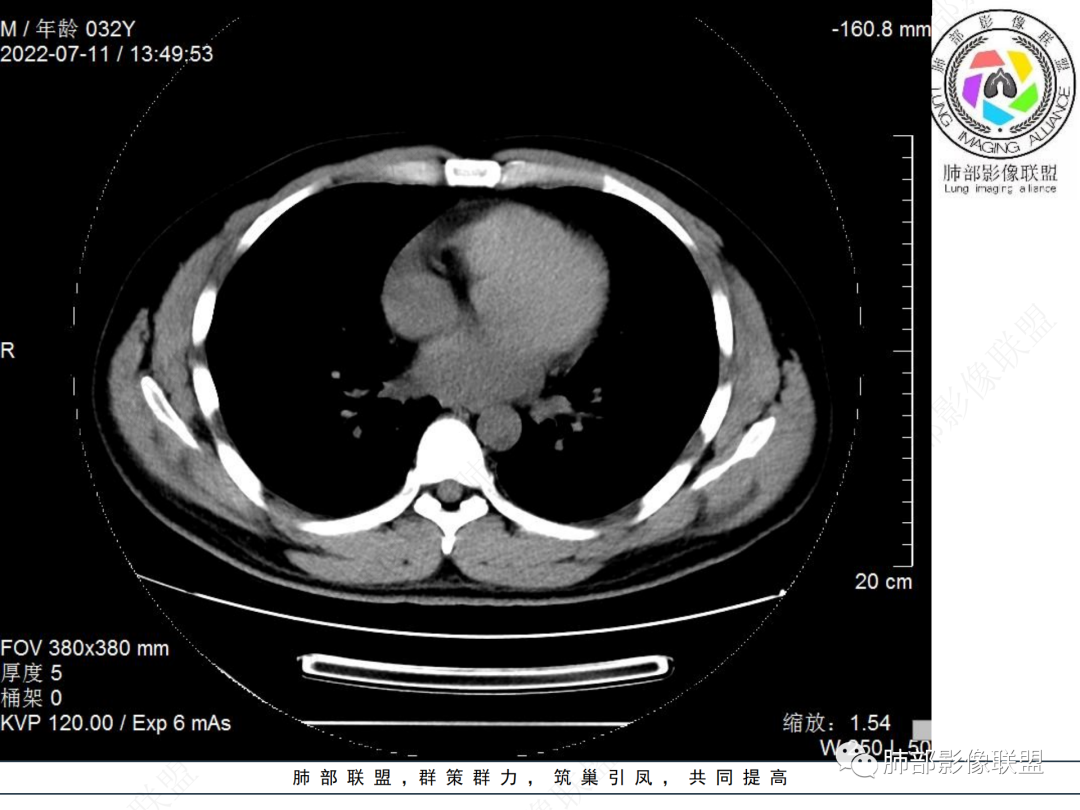

左肺下叶后基底段开口处结节,边缘光滑清楚,没有增强扫描,年轻男性患者痰血三天,考虑1.良性病变:腺瘤、错构瘤、平滑肌瘤

2.恶性:类癌、粘液表皮样癌。

左肺下叶外后基底段气管内见结节状影,边缘部分清晰。考虑错构瘤,待排恶性病变。

左肺下叶气管内外占位病变,咯血病史,考虑类癌,粘表待排。

青年男性,左肺下叶后基底段支气管开口软组织结节,边缘光整,气管镜提示质软,易出血,考虑类癌

左肺下叶后基底段开口处腔内见壁结节,花生米样,宽基底,补充增强及矢状位重建,确定我无向壁外突破浸润生长,另见强化的特点,临床触之易出血,类Ca可能性大。

年轻男性,咳血,左肺下叶后基底段支气管腔内结节,边缘光滑,首先考虑青年三件套,类癌大于粘液表皮样癌,支气管镜质软,触之易出血,鉴别血管瘤,平滑肌瘤

左肺下叶后基底段开口部结节,密度较均匀一致,边缘较光整,目测密度偏低,支气管镜示:质软、触之易出血,考虑恶性,类癌。

支气管腔内结节,有蒂与支气管壁连接,考虑良性病变可能性大,支气管错构瘤 血管瘤一类的

左肺下叶后基底段支气管腔内结节,有蒂,容易出血,先考虑良性病变,肉芽组织型血管瘤,与类癌鉴别。

青年男性,左肺下叶后基底段支气管开口软组织结节,边缘光整,气管镜提示质软,易出血,考虑恶性类癌

左肺下叶后基底段开口处结节影,边缘光整,年轻患者,伴咯血,考虑鳞癌,类癌不能排除